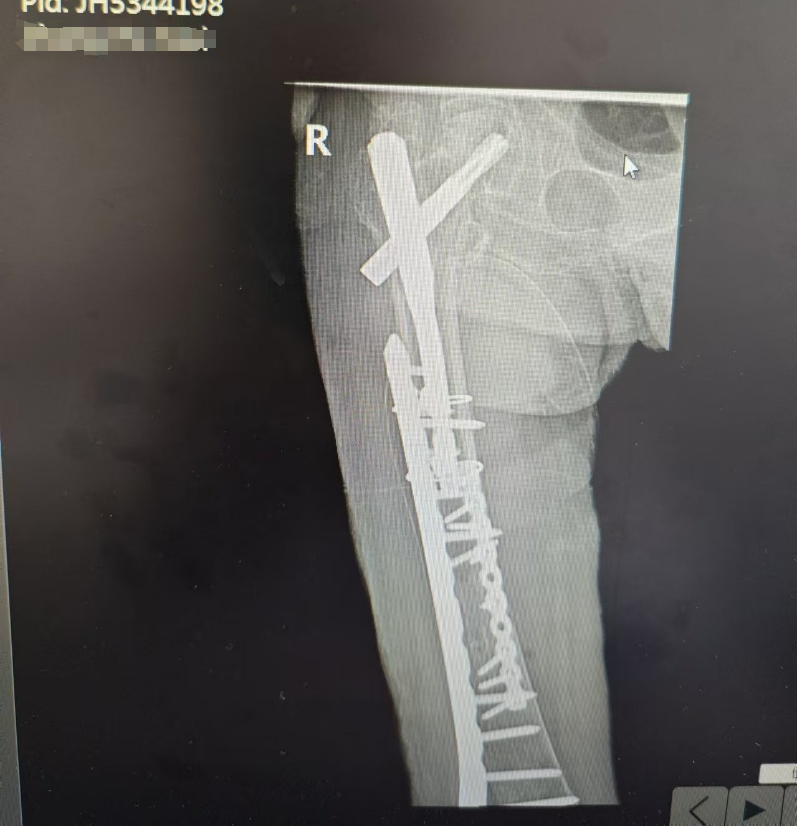

鉴于张奶奶的高龄、多种基础疾病以及骨折情况的复杂性,术前特别组织了多学科专家的深入讨论。随后为她实施了股骨骨折的切开复位钢板内固定手术,术中采用腰麻,维持血流动力学和内环境稳定,控制出入量,保持氧供需平衡,在原有髓内钉的基础上,予以双钢板牢固固定,基本实现解剖复位。

复查术后 x 线片提示:内固定在位,骨折对线对位良好。换药见切口愈合良好。